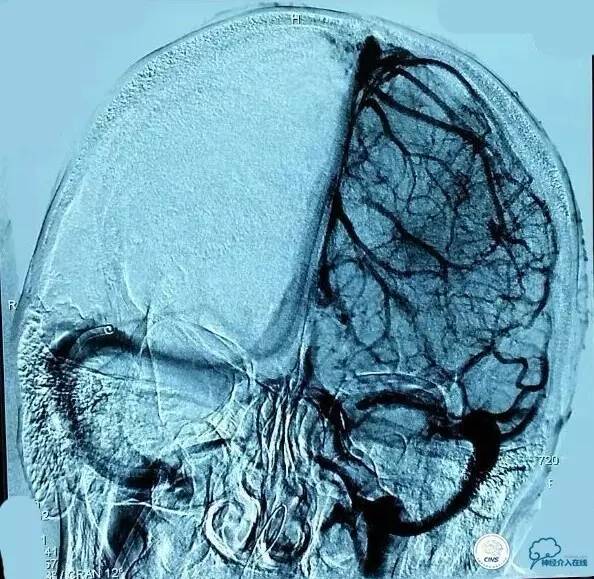

▼第三次取栓后造影,窦通畅,下矢状窦显影延迟,说明上矢状窦通畅了。

▼正位: